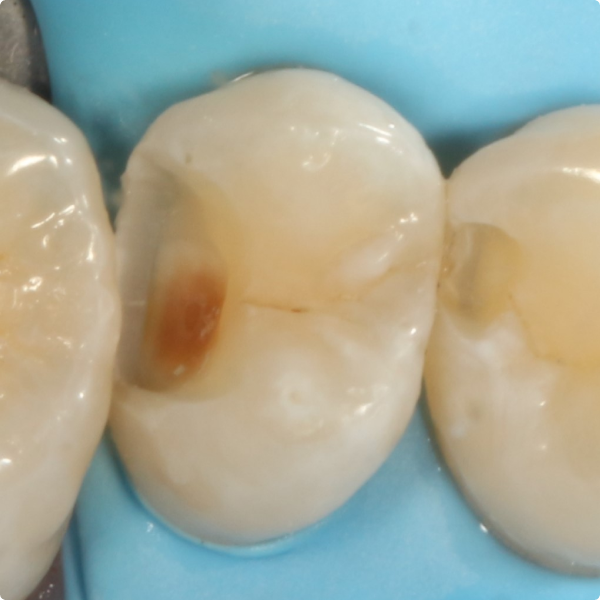

When a 17-year-old patient arrived for a routine six-month check at Dr Kiran Shankla’s practice, there were no complaints or concerns raised by the patient. During the examination a subtle colour change was observed on the upper left premolar. A bite-wing X-ray revealed a cavity, further confirmed with the aid of software.

Although Stela can be used without a rubber-dam, Dr Shankla opted for one to maintain optimal isolation and control. After removing the decayed tissue, photographs were taken to document the cavity’s extent. A sectional matrix was placed to ensure proper contact, given the size of the lesion, then the Stela system was applied.